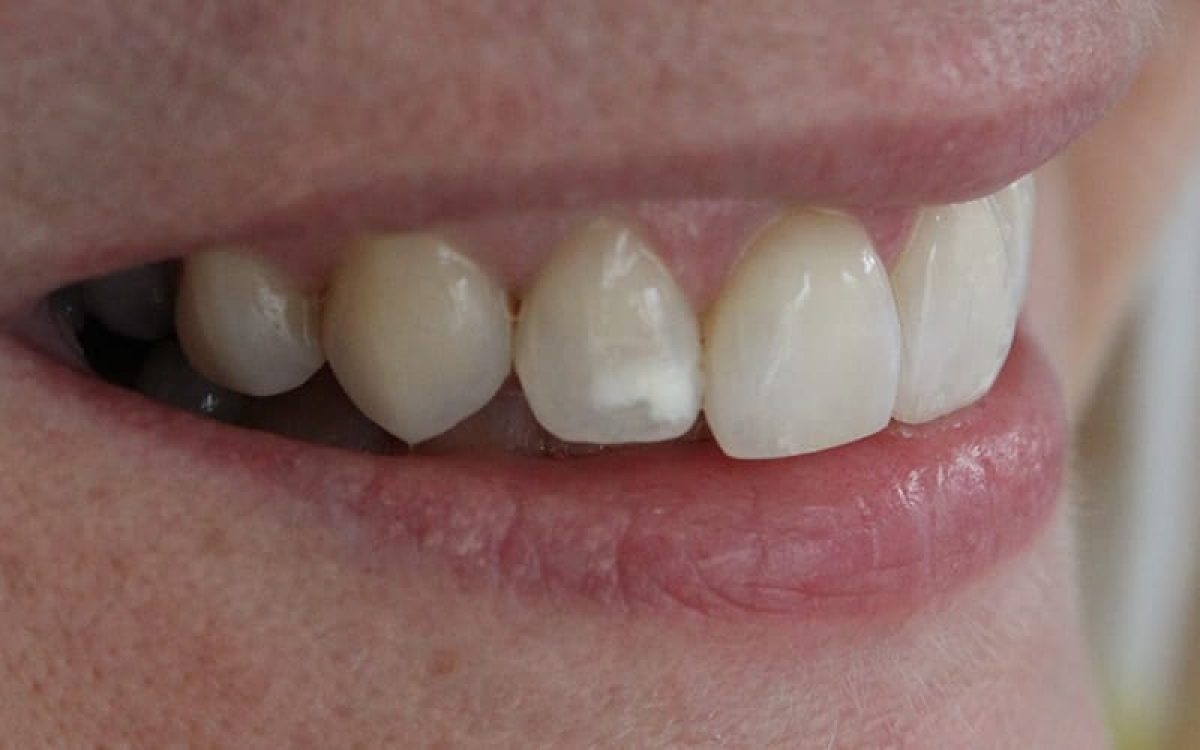

Clinical Definition and Appearance

White spots on teeth are small, lighter patches on your teeth. They show up when the enamel starts to break down. This can happen due to bad dental care, too much fluoride, or enamel hypoplasia.

These spots can show up on any tooth surface. They might be more visible on your front teeth.